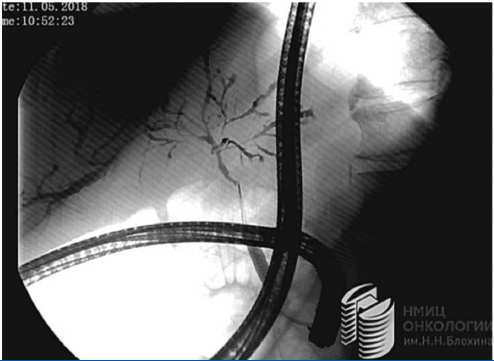

Пациенту с диагностической целью выполнены дуоденоскопия, папиллосфинктеротомия, ЭРХПГ, холангиоскопия, щипцовая биопсия.

При рентгенографическом (РГ) исследовании – при тугом контрастировании данных за расширение желчных протоков не получено. Интрапанкреатическая часть общего желчного протока до 5–6 мм, стенка ровная. На уровне средней и верхней трети холедоха стенка узурированная, неровная, просвет нитевидный, извитой. Долевые протоки также с неровными контурами и нитевидным просветом. Неровность стенки прослеживается до сегментарных протоков. Рисунок внутрипеченочных желчных протоков при тугом контрастировании резко обеднен.

Пациент консультирован химиотерапевтом – назначена полихимиотерапия (ПХТ) по схеме GEMOX (рис. 4).

Рис. 4а. Изображение ретроградной холангиографии.

Fig. 4a. ERCP image.

Рис. 4б. Изображение транспапиллярной холангиоскопии с помощью системы SpyGlass.

Fig. 4b. SpyGlass image.